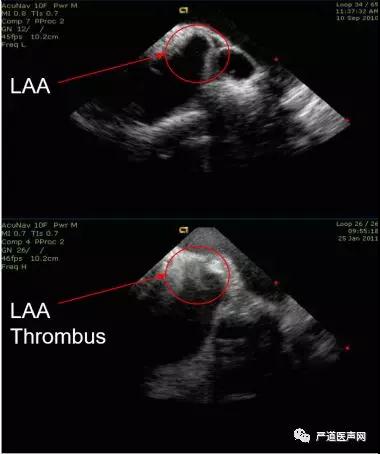

第四步:RVOT位置时视野,排除心耳血栓;肺动脉瓣上视野,初步评估左心耳开口。

以mid-RV位置为初始,释放张力控制旋钮和回复P/A和L/R 旋钮至中位的前提下,顺时针旋转导管至可见主动脉短轴和肺动脉长轴,继续轻柔推送导管以防出现弯折,必要时适当调整张力旋钮和A弯直至通过肺动脉瓣。

图5 RVOT位置时视野

(可判断是否有血栓形成,下图为左心耳内有血栓)

图6 RVOT位置时视野

(左图红圈为左心耳,右图为三维超声建模和扇面展示)